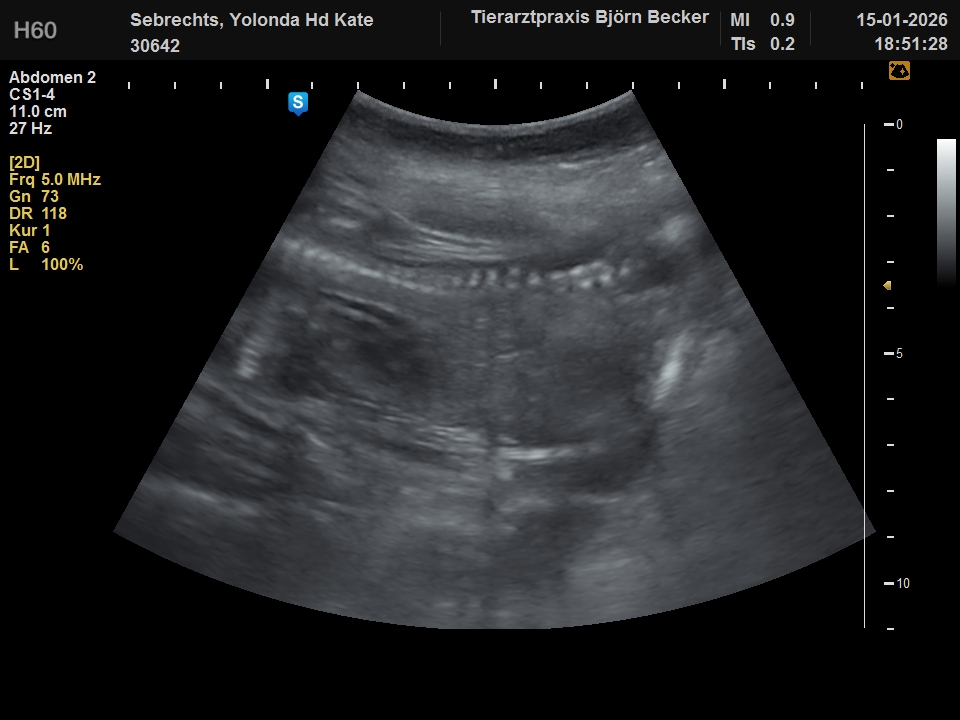

Donderdag 15-01-2026 zijn we met spoed naar de dierenarts geweest. Kate Had wat vruchtwater en slijm verloren. Gelukkig was er niks ergs aan de hand en kwam dit omdat ze veel vruchtwater bij zich heeft. Daarna is er een echo gemaakt. Jullie kunnen nu alvast kennis maken met de puppies terwijl ze nog in de dikke bolle buik van Kate zitten. 6 puppies wilde zich laten zien op de echo en nummer 7 was te verlegen. Over enkele dagen kunnen we ze in het echt zien. Ben je geïnteresseerd en lijkt het je leuk om de puppies te ontmoeten, maak dan een afspraak. De eerste drie weken gaan Kate en wij eerst zelf volop genieten van de puppies. Daarna zijn jullie van harte welkom.

De verlegen pup